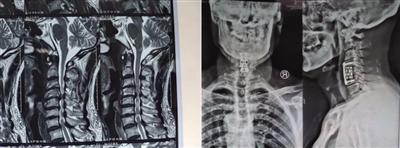

脊髓型颈椎病术前术后影像学。

该科不仅着力提升微创手术治疗的技术,还注重以中西医结合的方法,为患者提供全面的个性化治疗。53岁的邓先生头晕、颈项痛间歇发作4年多,辗转就医未果,去年病情加重,伴有双上肢麻木、行走不稳,在朋友的推荐下来到该院就诊,经过进一步检查,尹立刚诊断其为脊髓型颈椎病。于是,为其施行全麻下前路C4/5、C5/6髓核摘除椎间融合脊柱内固定术。术后第二天,邓先生右上肢麻木症状消失,第五天,即可戴着颈托下地活动。此后,该科辅以中药、中药外治手法助其康复,两周后,邓先生完全恢复自主活动。